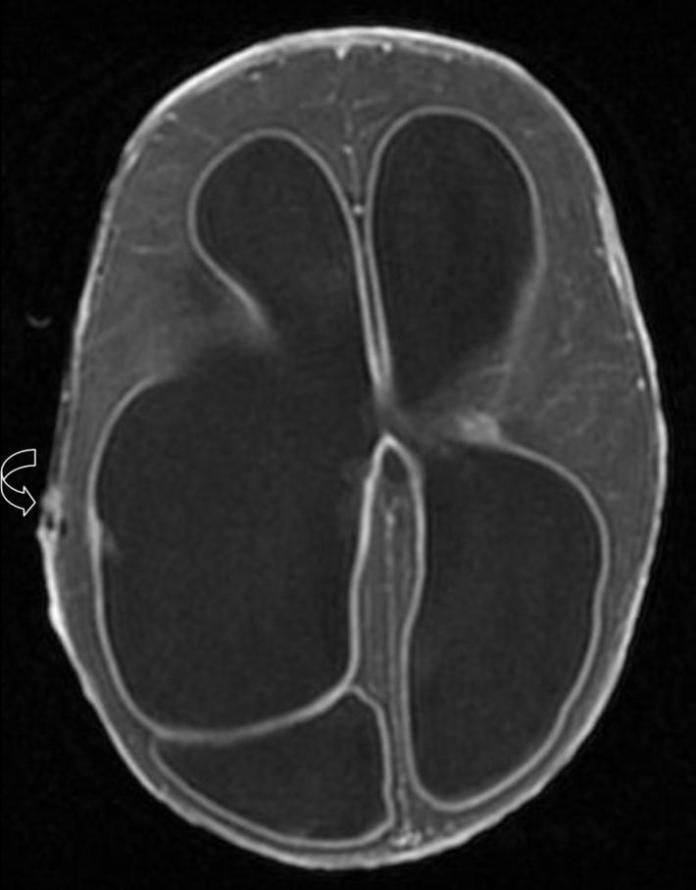

The above case shows enlarged ventricles with diffuse smooth ependymal enhancement and internal septum. Arrow denotes previous shunt tube.

MR Findings:

-Ventriculomegaly,

-Dependant debris (high T1 and low T2 signal),

-Marked ependymal enhancement,

-Internal septa and loculations (in chronic cases),